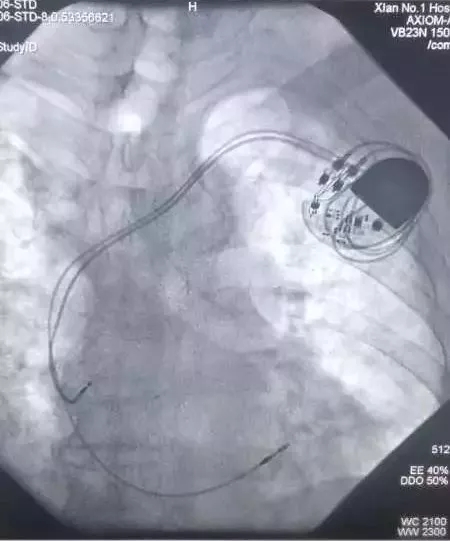

CCU成功实施我院首例双主动电极抗核磁起搏器植入术